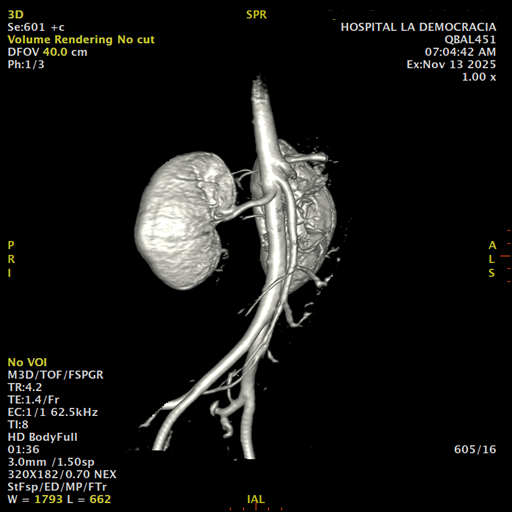

Paciente de sexo femenino, de 45 años de edad, refiere infecciones urinarias a repetición, no hay dolor, no refiere trauma, consulta por ardor al orinar, medico tratante le solicita resonancia abdominal, con énfasis en riñones, además un estudio de angiorenal.

Se prepara a paciente para ingreso a zona 4 del área de resonancia. Se coloca a paciente en decúbito supino, se canaliza en vena antecubital, se utiliza bobina de abdomen de 16 canales, se adquieren localizadores en tres planos, luego se procede a adquirir imágenes en diferentes planos, con secuencias echo spin y eco de gradiente, potenciadas a T1 y a T2.

Los sistemas colectores del riñón derecho y del riñón izquierdo, muestran alteración de sus calices primarios y secundarios, mostrando dilatación, la pelvis renal y el uréter se observan de características normales lo que indica que no hay proceso obstructivo.

Se observa dilatación del sistema calicial sin proceso obstructivo compatible con una anormalidad del desarrollo de los sistemas colectores de ambos riñones, definiéndose como una “megacaliosis”